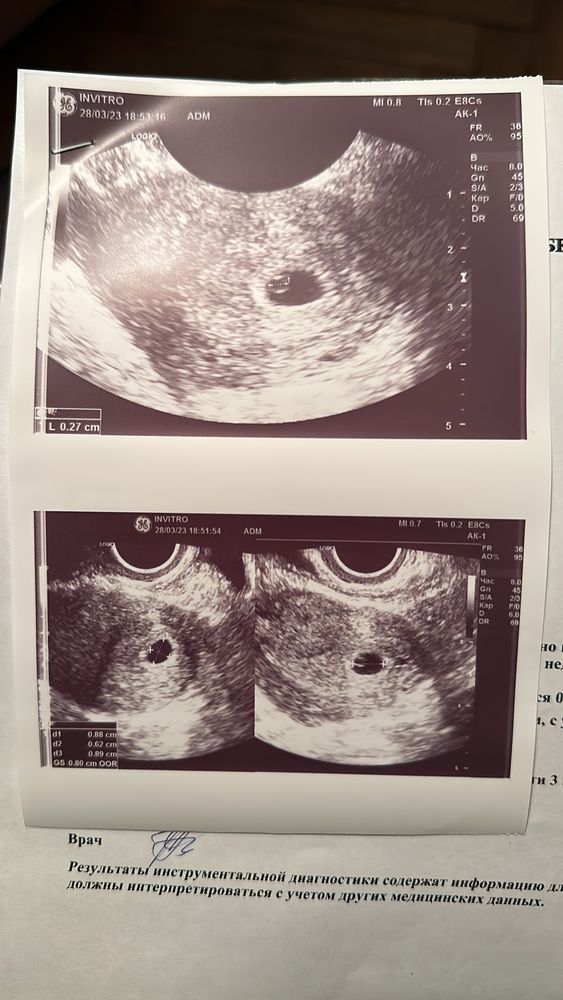

Девочки пожалуйста подскажите, может у кого то так было, у меня срок по узи не соответствует сроку по месячным(9 февраля дата последних месячных),узистка говорит, что такое может быть если овуляция была поздняя, но мне как то не по себе, вдруг это плохо

Алёна, нормально у вас все. У вас диаметр плодного яйца 8 мм, это как минимум 5-6 недель. Может, ваш узист не знает, что аппарат показывает срок не акушерский, а скорее от зачатия.